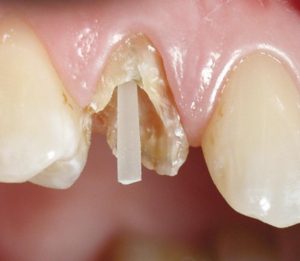

Wklady z włókna szklanego – zwiększają utrzymanie i zakotwiczenie dużych wypełnień w zębach .

wklady z wlokna

Wkłady korzeniowe z włókna szklanego.

wklady

Wkład z włókna szklanego zamontowany w korzeniu zęba.